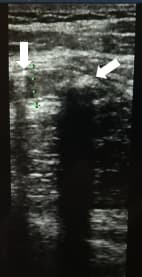

Воспаленный аппендикс не поддается компрессии, поэтому его размер и форма остаются прежними (трубчатая структура на продольном скане и круглая на поперечном) (см. рис. 4).

Рисунок 4. Оценка сжимаемости.